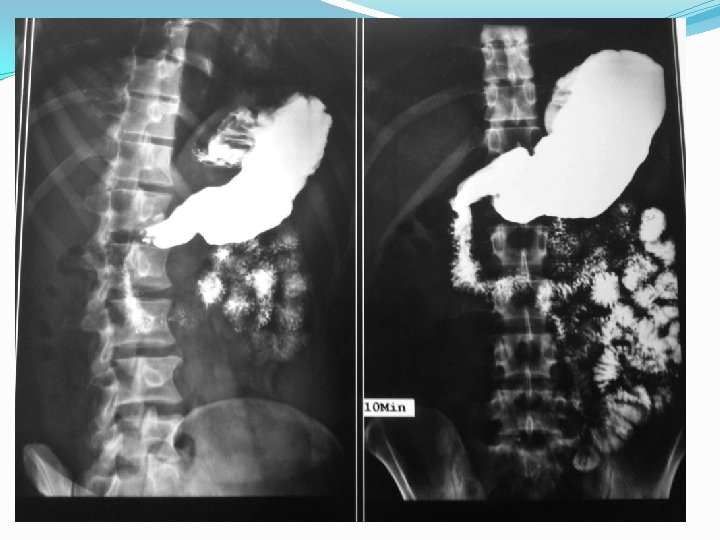

Barium studies of the gastrointestinal tract may suggest the diagnosis but are neither sensitive nor specific. They typically reveal thickening or nodularity in the antrum and a thickened or "sawtooth" mucosa in the small bowel.